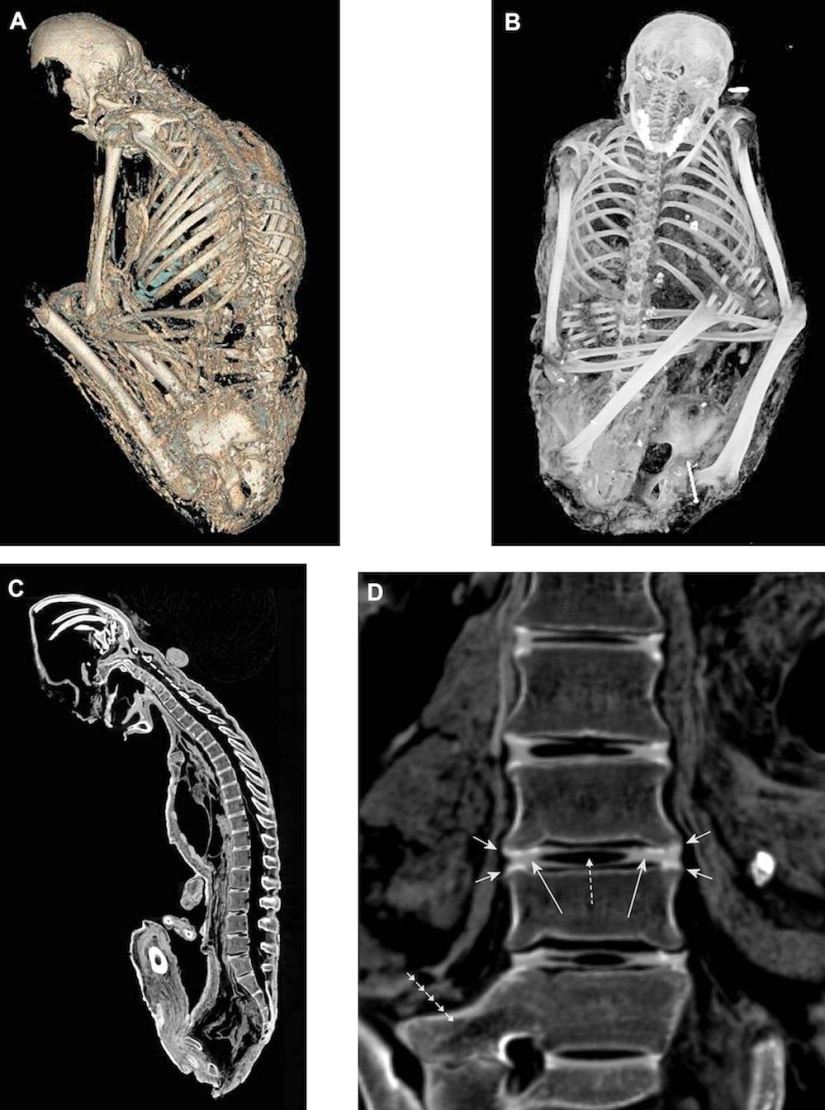

Una radiografía del cerebro de una niña de 6 años mostró que fue alcanzada por un rayo. Sus órbitas con ojos, nervios ópticos (flechas) y músculos visuales se muestran aquí.